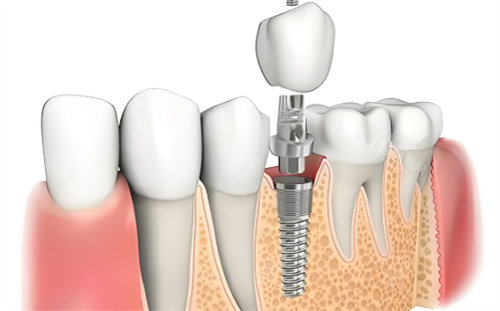

种植牙系列:

韩国DIO种植牙:1290元起

韩国登腾种植牙:2090元起

德国朗斯种植牙:3270元起

瑞士ITI种植牙(士卓曼):5090元起

沈阳国民口腔医院汇聚了一批经验充足的口腔医师,每位医生都经过严格筛选和特色培训。我们的种植牙医生拥有数千例成功实例,熟练掌握各种复杂种植技术,包括即刻种植、小创口种植、All-on-4/6等较高技术。矫正医生精通各类矫治技术,能够为不同年龄段的患者制定个性化矫正方案。